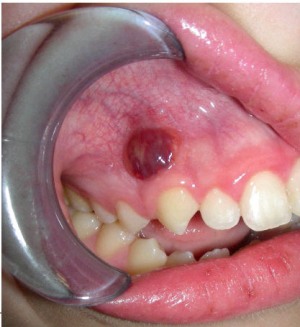

Симптомы флюса: нестерпимая зубная боль и опухание в очаге воспаления вплоть до значительного увеличения щеки. Для устранения этих признаков проводят хирургическое вмешательство.

- Острый гнойный флюс выявляет себя острыми пульсирующими болями, иррадирующими в глаз, висок, ухо. Слизистая оболочка краснеет и отекает, а также повышается температура до 38,5оС. В процессе развития гнойного содержимого симптомы периостита только усиливаются. Причинами заболевания также могут быть открытые переломы на других костях, а не только челюстной. Гнойное воспаление может случиться при варикозном расширении вен, трофических язвах голени, слоновости, тромбофлебитах. Кроме того, причинами острых и хронических воспалений надкостниц голени могут стать разрывы сухожилий, аллергические воспаления, ревматизм, воздействие токсинов.